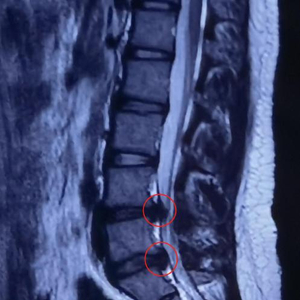

经过系统专科查体及影像学检查,发现茜茜的腰4/5、腰5/骶1椎间盘膨出,已压迫到腰5、骶1神经根。如选择保守治疗,突出的髓核在短时间内无法自吸收,且有进一步加重进而压迫到马尾神经的风险,于是,董黎强团队决定为茜茜施行“椎间孔镜下腰椎间盘突出髓核摘除”微创手术。